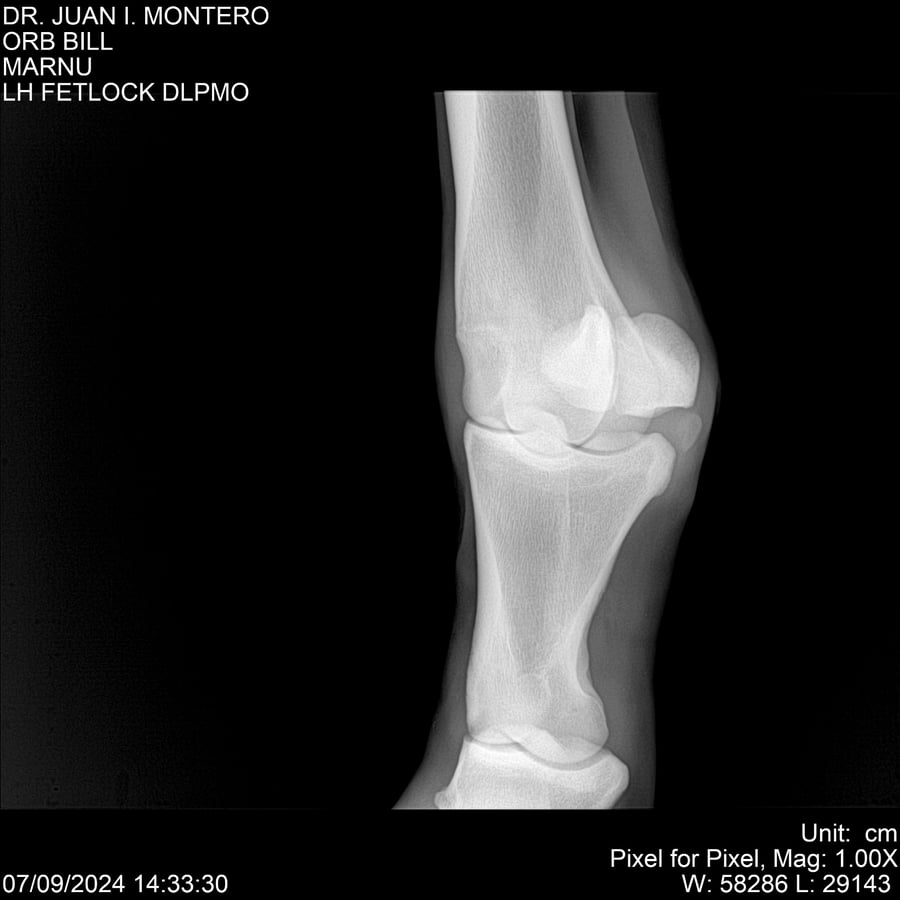

LOTE 7, ORB BILL 🔥 🔥 🔥 Lote Anterior Volver al remate Lote Siguiente Ficha Contacto Montevideo - Ficha del Lote Identificador: #282523 Categoría: Yeguarizos Montevideo - 83 Visualizaciones ClicData Contacto Empresa: Abelenda N. R., Walter Hugo Nombre*: Teléfono* : E-mail* : Mensaje Enviar Registrese gratis Este contenido Exclusivo está disponible sólo para usuarios registrados Ingresar